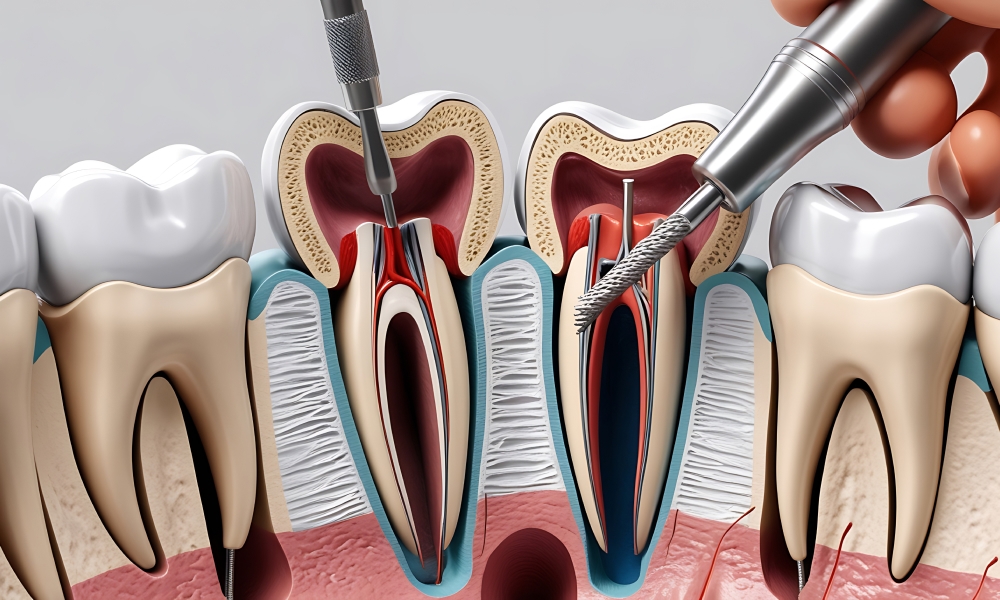

Nezihdent olarak, ağız ve diş sağlığınızı en yüksek standartlarda korumak ve estetik bir gülüşe kavuşturmak için buradayız. Modern teknoloji, hijyenik ortam ve uzman kadromuzla, her hastamız için özel bir tedavi süreci planlıyoruz. Amacımız, yalnızca dişlerinizi tedavi etmek değil; sizi daha sağlıklı, mutlu ve kendine güvenen bir birey haline getirmektir.

Sunduğumuz hizmetlerde güven, samimiyet ve hasta memnuniyeti önceliğimizdir. Diş sağlığı yolculuğunuzda sizinle birlikte yürümek ve her adımda destek olmak için buradayız. Sağlıklı gülüşler, mutlu yarınlar için sizleri kliniğimize bekliyoruz.